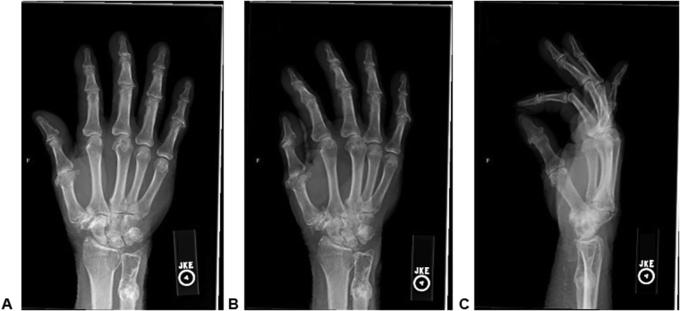

骨内肿瘤性二水焦磷酸钙晶体沉积病诱发的罕见病理性尺骨骨折

An Unusual Pathologic Ulna Fracture Induced by Intraosseous Tumoral Calcium Pyrophosphate Dihydrate Crystal Deposition Disease.

In this case report, we describe a novel occurrence of tumoral calcium pyrophosphate dihydrate crystal deposition disease (TCPPDCD) in a 76-year-old man that presented as an unusual, intraosseous, metadiaphyseal lesion of a long bone causing a pathologic fracture. A routine intralesional biopsy was performed, demonstrating granular deposits composed of polarizing, overlapping rhomboid crystals consistent with TCPPDCD. With limited numbers of reported cases of TCPPDCD, and the atypical intraosseous origin seen in this case, it is paramount to thoroughly evaluate all cases of TCPPDCD to clearly differentiate key findings that are essential in diagnosing and managing TCPPDCD.

在本病例报告中,我们描述了一名76岁男性发生的新型肿瘤性焦磷酸钙二水合物晶体沉积病(TCPPDCD),其表现为长骨骨干中段不寻常的骨内病变,导致病理性骨折。进行了常规的病变内活检,显示出由偏振、重叠的菱形晶体组成的颗粒状沉积物,与TCPPDCD一致。鉴于TCPPDCD的报告病例数量有限,且本病例中出现非典型的骨内起源,对所有TCPPDCD病例进行全面评估以明确区分诊断和管理TCPPDCD所需的关键发现至关重要。